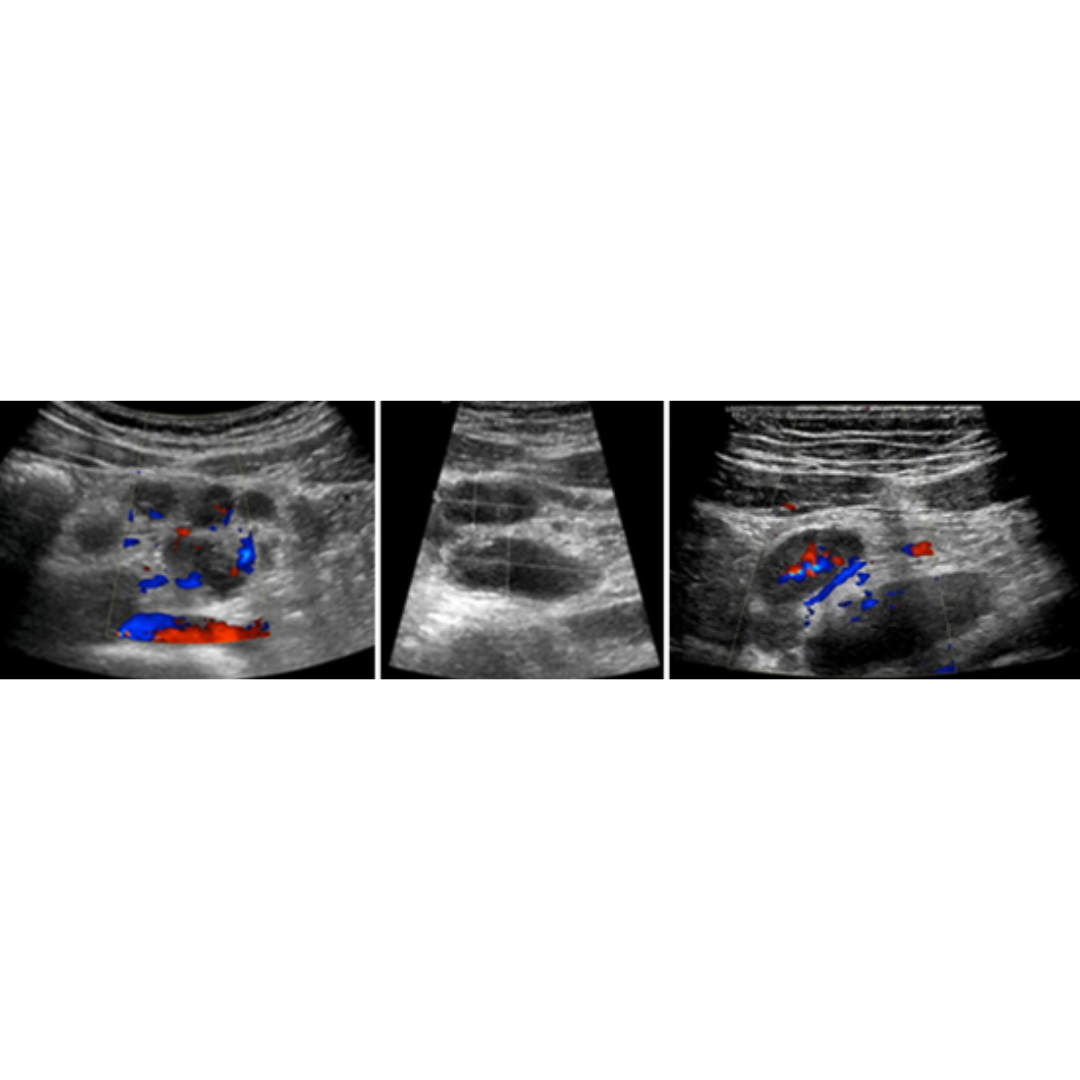

Adenitis Mesentérica

Es la inflamación de ganglios linfáticos del mesenterio, es considerado un signo en respuesta a inflamación y no un diagnóstico.

Signos US: aumento de tamaño de varios ganglios linfáticos (AP > 7 mm) presentes en FID y/o mesogastrio, con aumento de vascularización hiliar al Doppler color.

Figura 3: Múltiples ganglios aumentados de tamaño, se observa incremento de su vascularización hiliar.